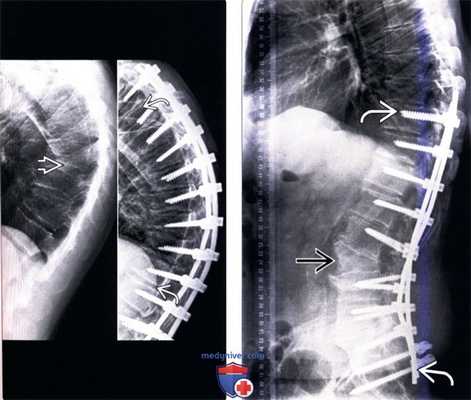

(Слева) Рентгенограмма в прямой проекции: случай ротационного левостороннею сколиоза поясничного отдела позвоночника с многоуровневыми дегенеративными изменениями межпозвонковых дисков и склерозом замыкательных пластинок. Здесь же виден боковой левосторонний листез L4 позвонка.

(Справа) На рентгенограмме в боковой проекции определяется сглаженность поясничного лордоза с многоуровневым дегенеративным поражением межпозвонковых дисков и дегенеративной эбурнеацией замыкательных пластинок, наиболее выраженной на уровне L2-L3. (Слева) КТ, фронтальная проекция: незначительно выраженная левосторонняя сколиотическая деформация на уровне L4-L5 с появлением «феномена вакуума» в области межпозвонкового диска и склерозом правых половин замыкательных пластинок. Высота межтеловых пространств на уровнях L3-L4 и L4-L5 снижена.

(Справа) Т1-ВИ: случай антелистеза L4 позвонка на фоне тяжелого дегенеративного поражения межпозвонкового диска с появлением «феномена вакуума». Признаки дегенеративных изменений дисков и замыкательных пластинок также можно наблюдать на уровнях L2-L3 и L5-S1. На уровнях L4-L5 и L5-S1 видны признаки выраженного стеноза спинномозгового канала.